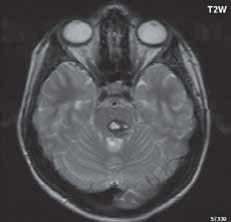

Obr. I.1.8h Mega cisterna magna

Obr. I.1.8ch Retrocerebelární vak (Blake’s pouch cyst), široce komunikující IV komora, chybí foramen Magendii